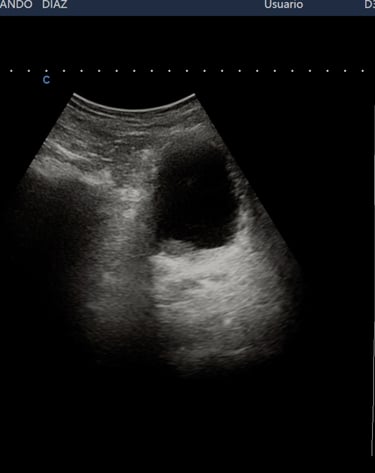

Por el costo de una ecografia, aprovechando nuestros conocimientos, experiencia y tecnologia te exploramos el abdomen total, el tiroides y carotidas

ECOGRAFIA O ULTRASONIDO DE TODO EL CUERPO

Ultrasonido y Densitometría

Estudios de ultrasonido y densitometría para un diagnóstico completo y detallado.

Ultrasonido o Ecografia

APLICA PARA : CABEZA, CUELLO, TORAX, ABDOMEN Y EXTREMIDADES

GASTROENTEROLOGIA, ETC, ETC, ETC,,,,,,,,,,,

SIN LIMITE DESDE LA EDAD EMBRIONARIA

PIONEROS CON MAS DE 40 AÑOS DE EXPERIENCIA

PARA TODAS LAS EDADES

REALIZADA POR EXPERTOS

Galería Médica

Explora nuestros servicios de radiología y medicina regenerativa.